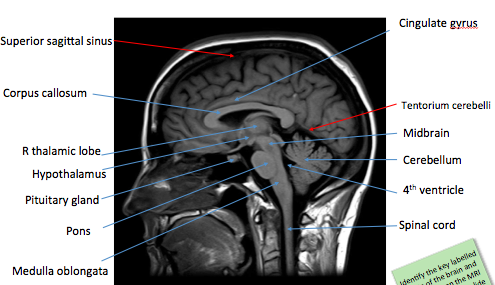

Label the image